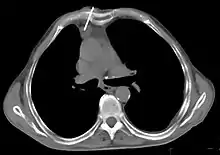

- Aspect scannographique

Présentation tomodensitométrique classique d'un thymome à un stade précoce (cercle rouge). À l'arrière, l'aorte, la veine cave supérieure et l'artère pulmonaire sont visibles en coupe.